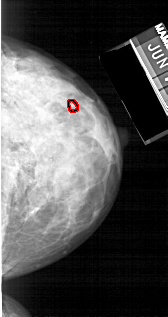

A_1220_1.LEFT_CC

LEFT_CC LINES 5296 PIXELS_PER_LINE 2761 BITS_PER_PIXEL 12 RESOLUTION 43.5 NON_OVERLAY

FILE: A_1220_1.RIGHT_CC.OVERLAY

TOTAL_ABNORMALITIES 1

ABNORMALITY 1

LESION_TYPE CALCIFICATION TYPE PLEOMORPHIC DISTRIBUTION CLUSTERED

ASSESSMENT 4

SUBTLETY 3

PATHOLOGY MALIGNANT

TOTAL_OUTLINES 1

BOUNDARY